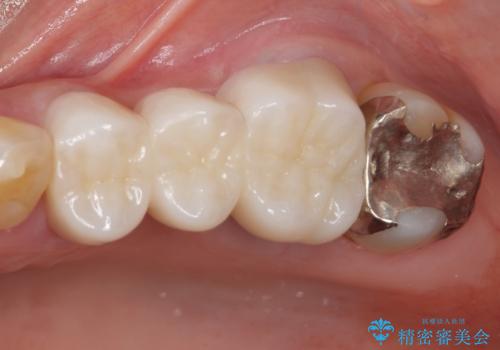

- 全顎的な歯列不正と、銀歯だらけの奥歯を気にして来院された患者様です。

奥歯の銀歯は、セラミッククラウンを装着するには歯の高さが不十分であり、そのままでは矯正治療を行うことが困難であるため、歯冠長延長術を行うこととしました。

また、根管治療の必要な歯がいくつかあるため、歯周外科治療の治癒期間を利用して根管治療を行い、その後インビザラインにて矯正治療を行うこととしました。